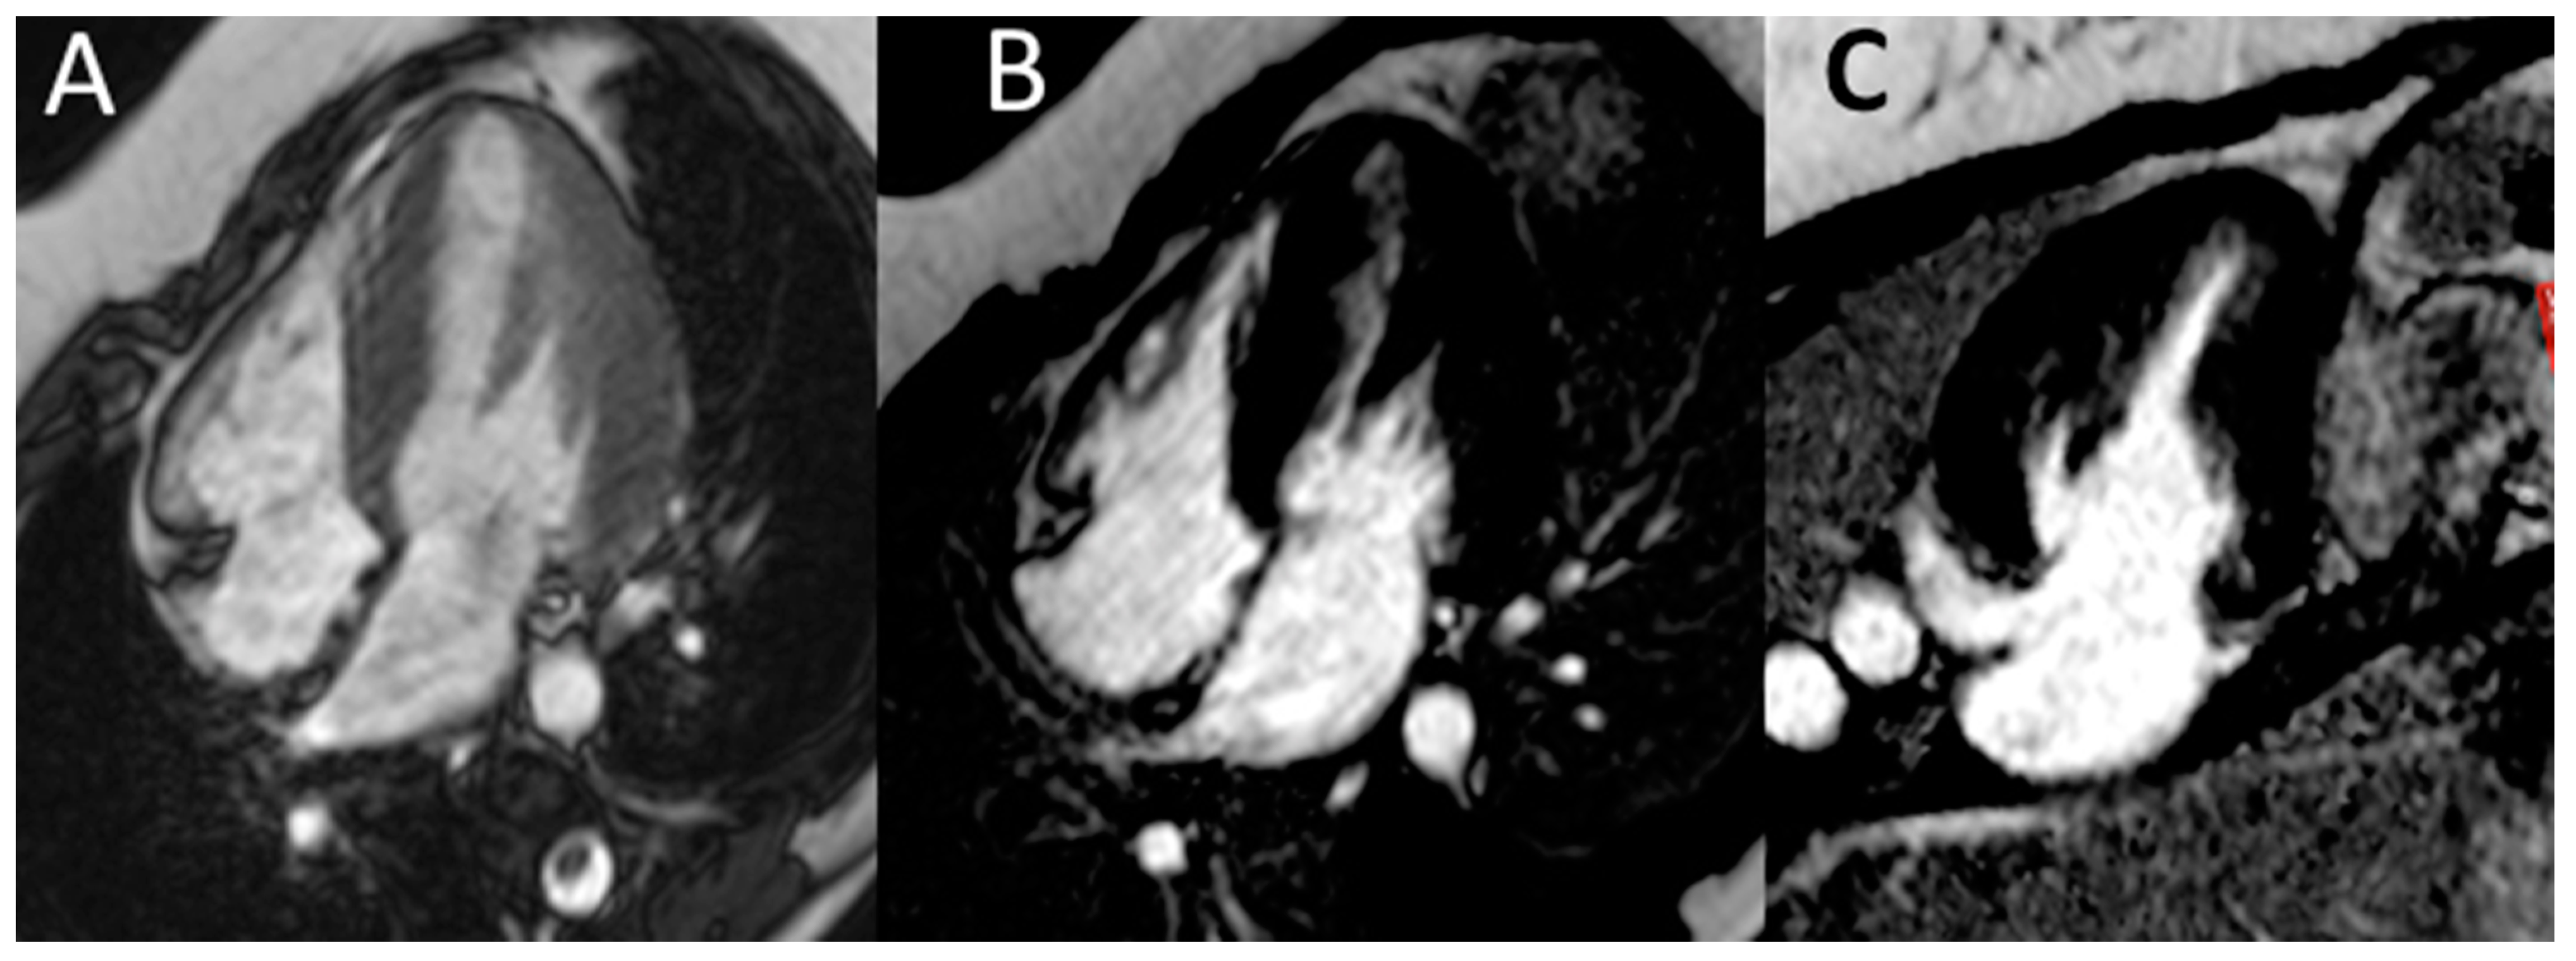

Electrocardiography suggested cardiac hypertrophy, confirmed at cardiac ultrasound, organised in the context of evaluations for kidney transplantation, which disclosed signs of relevant cardiac hypertrophy, out of proportion with her mild hypertension, confirmed at cardiac magnetic resonance (Figure 2, Figure 3 and Figure 4).

Figure 4. Cardiac magnetic resonance. Cardiac magnetic resonance (CMR) confirmed normal LV volume, systolic function and a moderate increase in LV thickness (panel A). No abnormalities in late gadolinium enhancement in the horizontal long-axis view (B) or vertical long-axis view (C) were found.